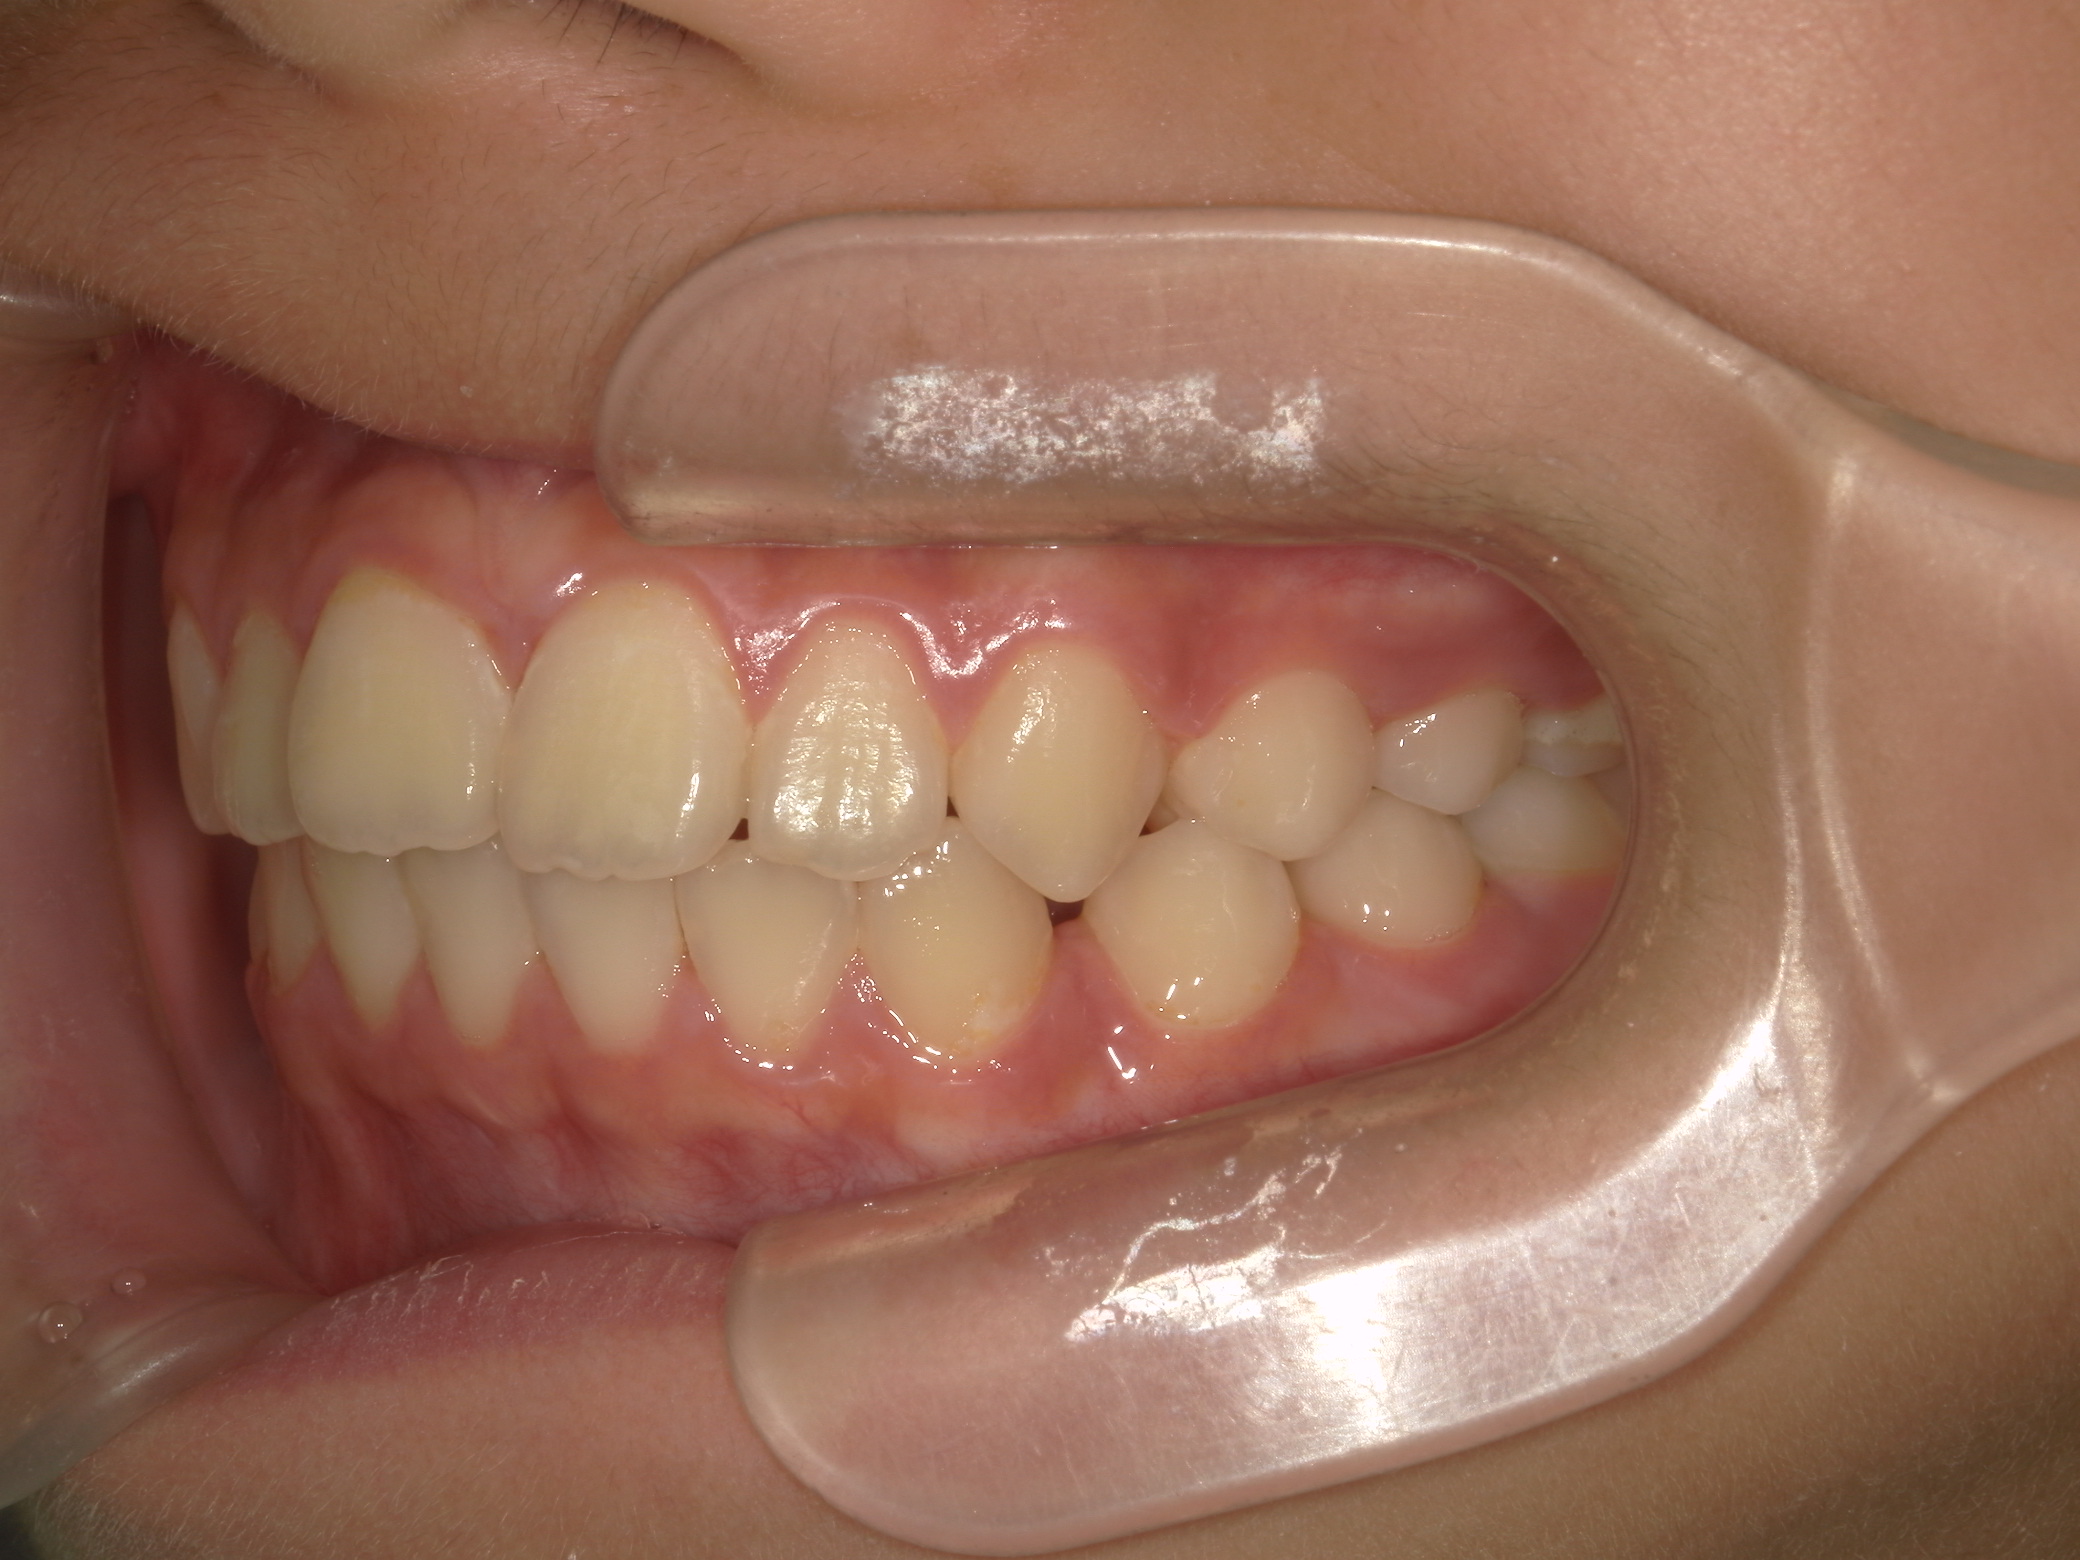

【小学生】マイオブレース矯正 開咬を改善

小学生で開始

マイオブレース

出っ歯

開咬

非抜歯

1期治療のみで改善

Before

After

治療期間

2年

治療開始

8歳

種類

マイオブレース矯正

使用装置

コメント

マイオブレースと 口腔筋機能療法で 咬み合わせが改善しました。

その後 装置を何も付けていませんが 後戻りしていません。

舌癖がある場合、後戻りしやすいですが、

口腔筋機能療法をきっちり取り組んでくれたので

リテーナーなど何も使用せずに安定しています。(AFTERの写真は5年後)